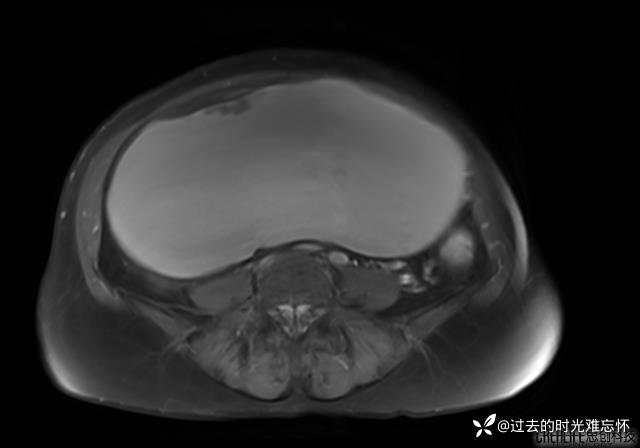

腹大能容5000液;术后腹部好轻松。妙手回春有结果。公布结果。

患者性别:女

患者年龄:65岁

主诉: 发现腹部隆起半年余。无其他明显不适。

浆液性囊腺瘤 (22)